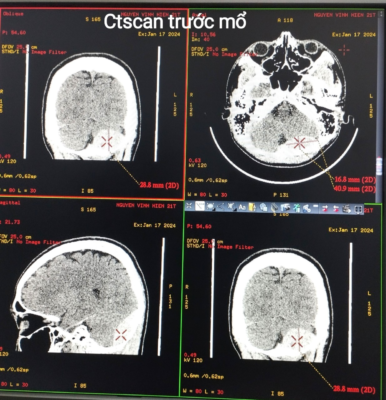

Hình 1. Kết quả cắt lớp vi tính sọ não sau chấn thương

Kết quả trên phim cắt lớp vi tính: vỡ xương chẩm, MTNMC hố sọ sau bên Trái, gây chèn ép tiểu não, bề dày khối máu tụ khoảng 17mm.

Trường hợp ca lâm sàng đến sớm, các triệu chứng tại chỗ được phát hiện ngay từ tại tuyến trước ngay sau chấn thương vùng chẩm. Vào cấp cứu tại Bệnh viện trong tình trạng ý thức còn khá tốt, tri giác theo thang điểm Glassgow 14 điểm, có sưng nề vùng chẩm Trái. BN được chỉ định chụp Ctscan sọ não ngay sau đó.

Chỉ định phẫu thuật áp dụng tiêu chuẩn chung của MTNMC cấp tính hố sọ sau, với tình trạng lâm sàng, kết quả hình ảnh cắt lớp vi tính, khối máu tụ gây đè ép đường giữa 17mm.